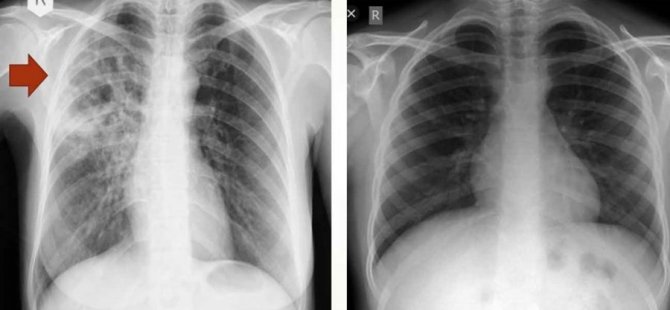

"Tüberkülozlu hastaların hem şikayetleri hem de bazen radyolojik görüntüleri deneyimli olmayan sağlık çalışanları tarafından Covid olarak yorumlanabilir. Bu durum hastaların tanı ve tedavisini geciktirmekte yattığı hastanede veya evinde bulaştırıcı olmaya devam etmesine yol açmaktadır.